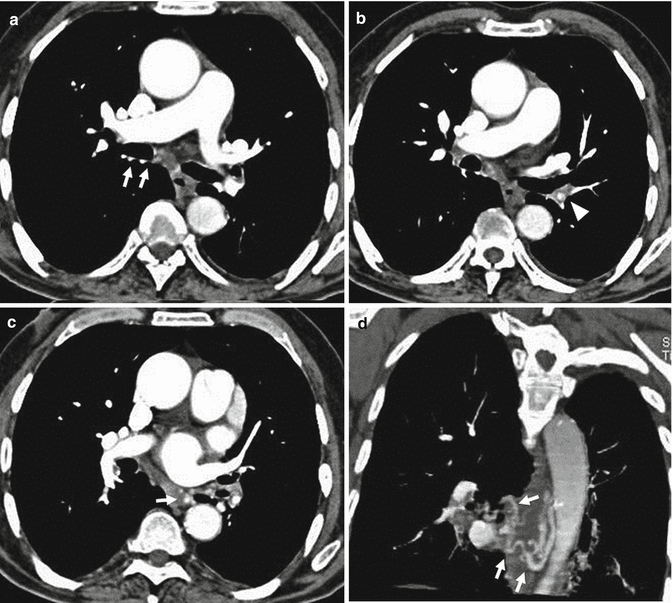

From www.researchgate.net

Pulmonary embolism (PE) of case 2 shown in the computed tomographic How Common Is A Pulmonary Embolism After C Section After all cesarean sections, women are given heparin and encouraged to get out of bed and walk as soon as possible. Pulmonary embolism during pregnancy and postpartum is one of the important causes of maternal mortality. The risk of vte was fourfold greater following cs than following vd; Pulmonary embolism (pe) is under diagnosed during pregnancy and. Pe is rare,. How Common Is A Pulmonary Embolism After C Section.